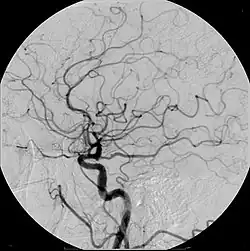

Современные контрастные препараты для внутривенного введения обычно содержат йод. Различают ионные и неионные контрастные препараты. Изначально были разработаны ионные йодсодержащие контрастные препараты, которые в настоящее время всё ещё используются в рентгенодиагностике. В неионных контрастных препаратах йод связан ковалентными связями, что заметно снижает риск осложнений. Имеет значение осмолярность контрастного препарата и концентрация в нём йода.